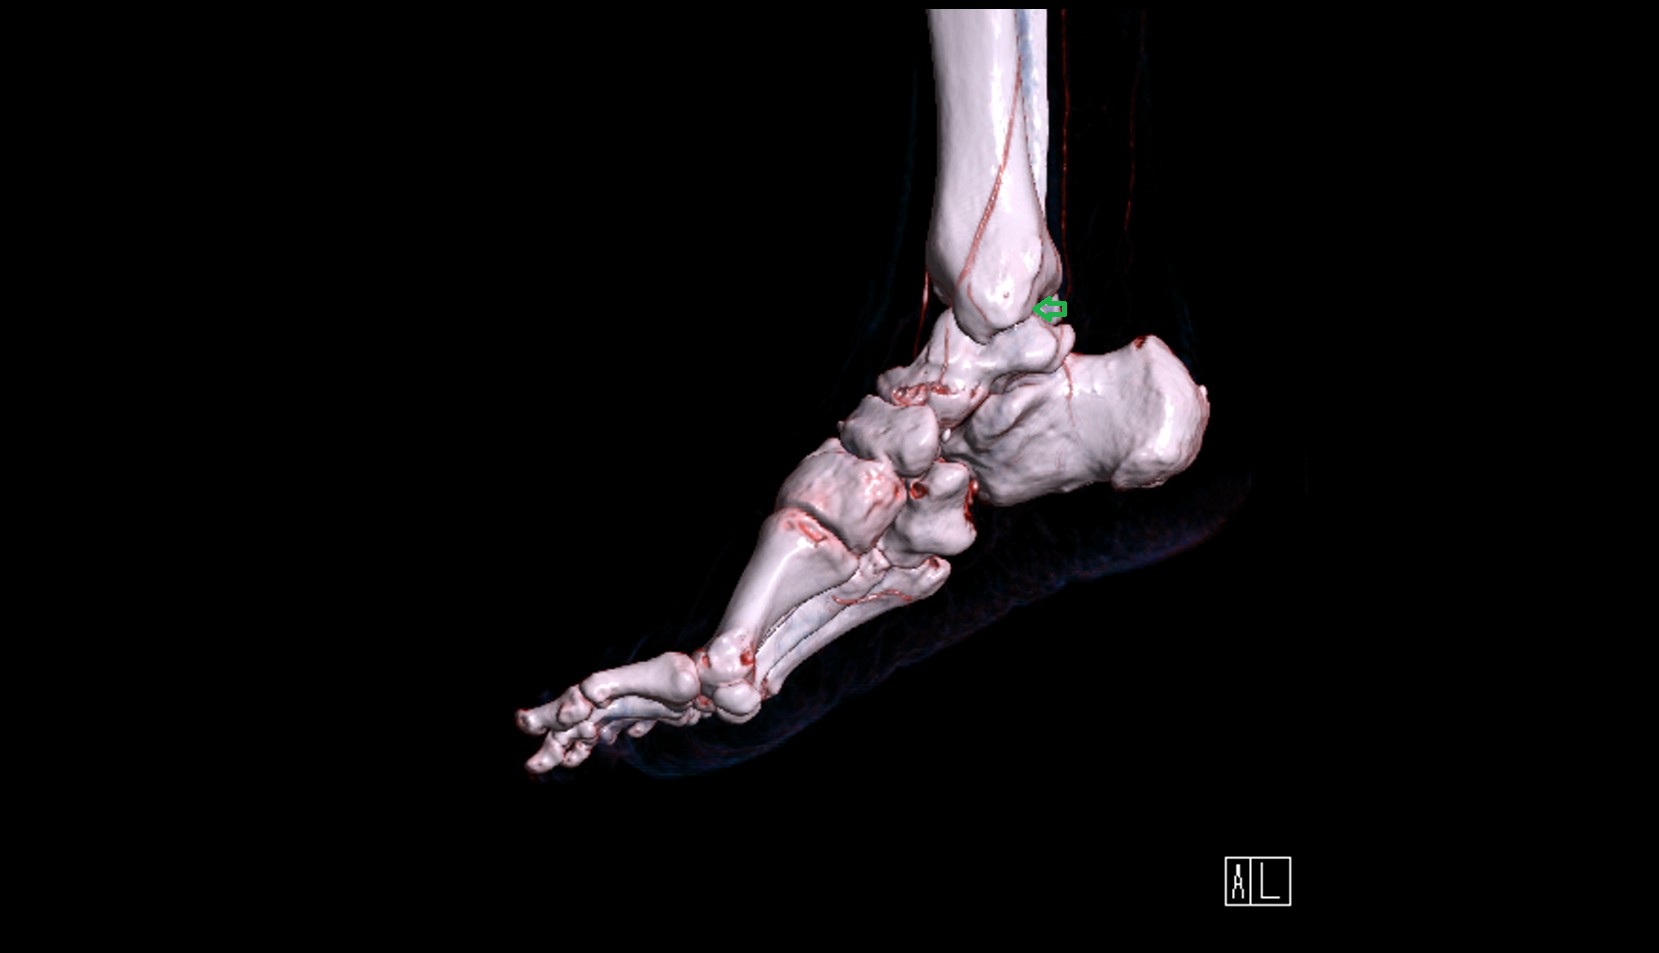

- Talus

- Head of talus

- Body of talus

- Neck of talus

- Calcaneus

- Anterior process of calcaneus

- Sustentaculum tali

- Cuboid

- Medial malleolus

- Lateral malleolus

- Ankle joint

- Talocalcaneal joint

- Talocalcaneonavicular joint

- Calcaneocuboid joint